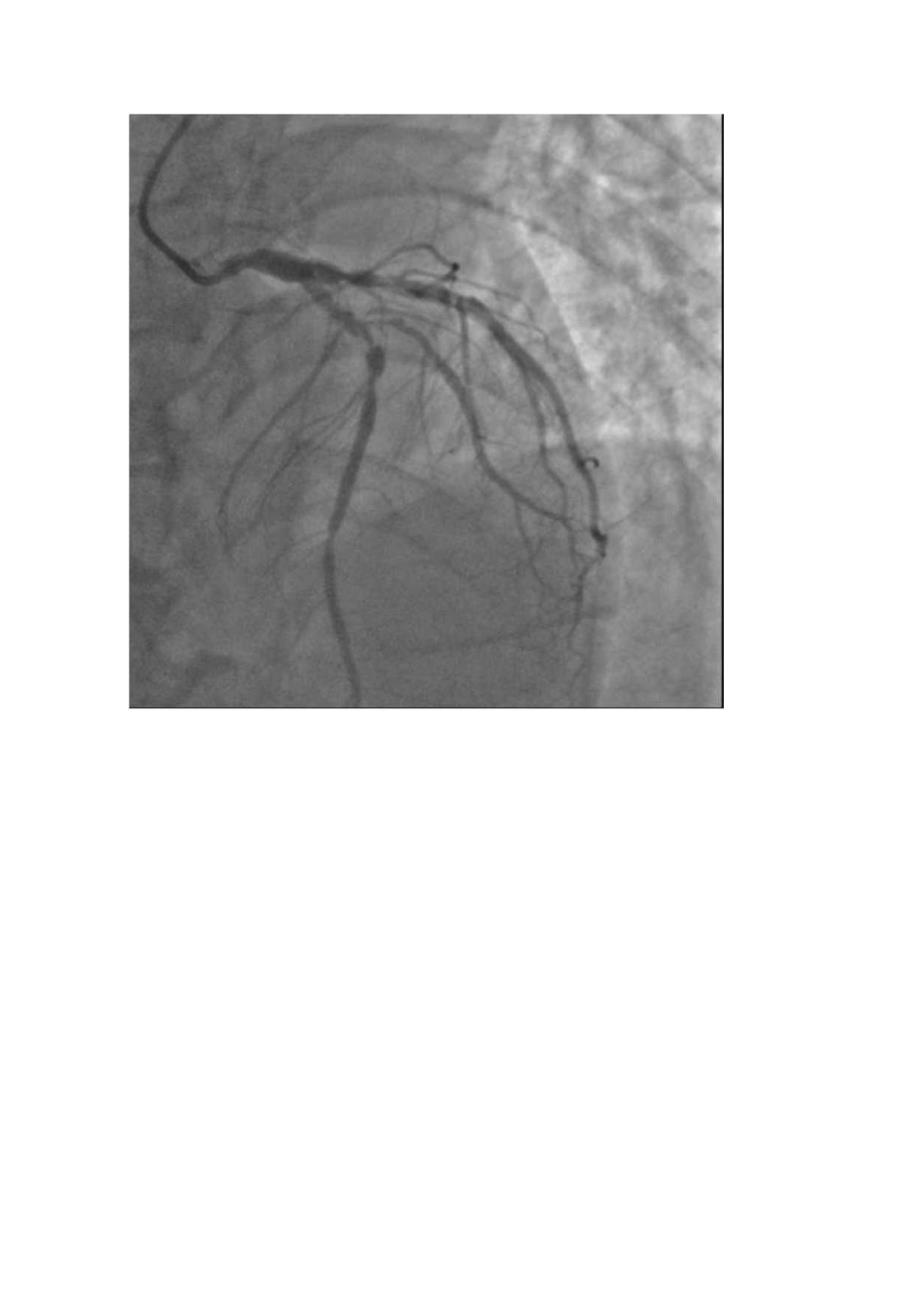

2、I呈QS型,V2/V3呈qRS型)心肌损伤标志物:肌红蛋白500ngml,CK-MB35.8ngml,肌钙蛋白4.54ngml;48小时主治医师诊断:初步诊断:急性前间壁心肌梗死,killipI级初步诊断:急性前间壁心肌梗死,killipI级1.M:开口及近段狭窄60LAD:近中段弥漫性长病变伴钙化,最重狭窄95%,第一对角支开口及近段钙化伴最重狭窄85%:LCX:近中段弥漫性长病变,最重狭窄90%,远段狭窄65%,RCA:近中段长病变,最重狭窄80%,远段狭窄60%。目前诊断“冠心病,三支病变”,建议外科搭桥术拒绝,接受分次PCl术。介入治疗过程:对LAD病变血管行PCh经鞘管插入7FEBU

3、3.5导引导管,经导管送入2Runthrough钢丝通过LAD至LAD及第一对角支远端,沿钢丝送入Ryujin2.0*15mm球囊至DI狭窄病变处,分别以4-6atm5秒扩张1次。退出球囊,沿钢丝送入SPrinterLegend2.5*15mm球囊至LAD近中段狭窄病变处,分别以8T4atm5秒扩张,复查造影示LAD近中段扩张欠满意,再取SeOrefIeX2.5*1Omnl球囊于LAD近中段狭窄钙化病变处,以12T8atm*5秒扩张,取3.5*18mmExcel,3.5*18mmExcel球囊支架至狭窄病变处,以1012atml0秒扩张释放支架,取Runthrough重置Dl导丝后,再用Sprinterl.5*15mm及CT02.5*IOmm于Dl以4-6atm*5秒扩张,再取DUraStar3.5*1OnIm高压球囊LAD支架内及支架连接处以14T8atm5秒后扩张,再造影未见残余狭窄。退出导管导丝,拔除动脉鞘管,无菌纱布覆盖,安返病房